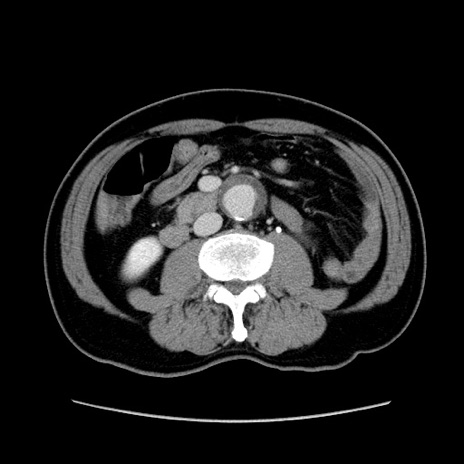

症例34(横断像)

【症例】60歳代 男性

【主訴】右鼠径部膨隆

【現病歴】1年程前より右鼠径部膨隆あり。自己にて還納可能だったため放置していた。3時間前より右鼠径部の脱出を認め、還納困難となり受診。

【既往歴】高血圧

【身体所見】右鼠径部に小児頭大の膨隆あり。弾性硬であり、用手還納は困難。左鼠径部にも膨隆を認める。脱出はなし。